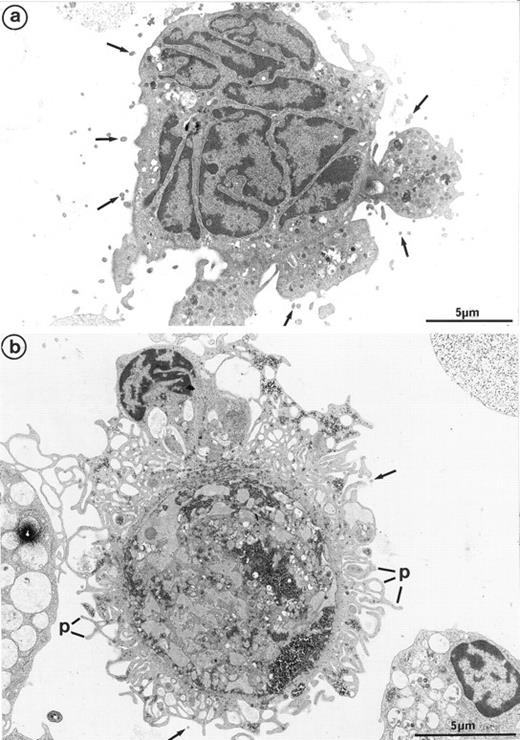

Interestingly, platelet-producing MKs were surrounded by numerous microparticles from 0.1 to 0.3 μm in diameter (Fig 7a). It is conceivable that the particles might be transverse sections of cell surface–connected pseudopods. However, they were also scattered in the vicinity of smooth areas of the plasma membrane and present along dilated channels of demarcation membrane with a smooth surface. These areas were devoid of pseudopods that could have been transversely sectioned. Moreover, these particles were not observed in the vicinity of thrombin-activated MKs, the surface of which was bristled with numerous long and thin pseudopods29 (Fig 7b). Some of these particles seemed to arise from fragments of the MK elongated arms, located between constriction zones, which were not included in the newborn platelet and were thus released into the surroundings. By immunoelectron microscopy, GpIIb-IIIa was also found to be strongly expressed on the shed microparticles.

(a) MK grown for 7 days from CD34+CD38+ progenitors in the presence of Mpl-l: numerous microparticles (arrows) surround this platelet-shedding mature MK. (b) Cultured MK having undergone thrombin activation (1 U/mL for 5 min): the plasma membrane is bristled with numerous pseudopods (p). However, unlike platelet-shedding MKs, only a few microparticle profiles are seen around the cell surface (arrows), probably corresponding to some pseudopod transverse sections.